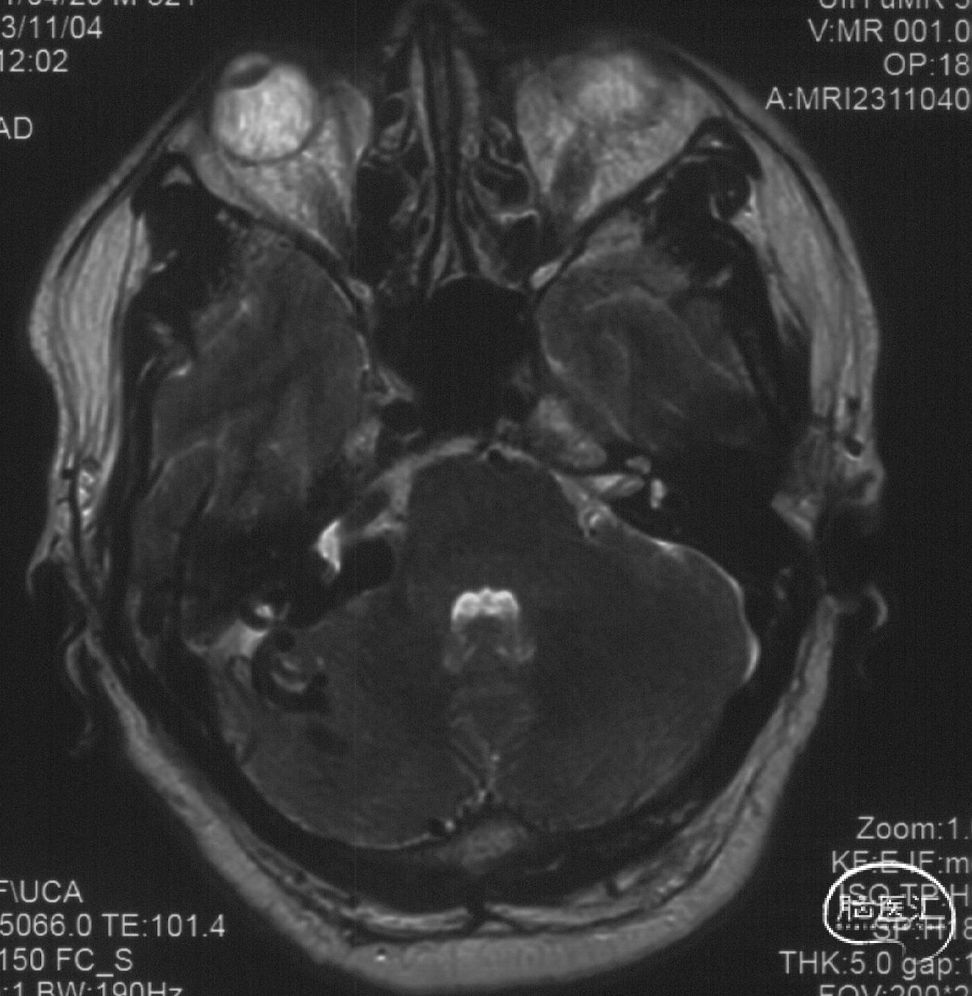

术前MRI

MRI见右侧桥小脑脚区、小脑幕旁多发血管留空影